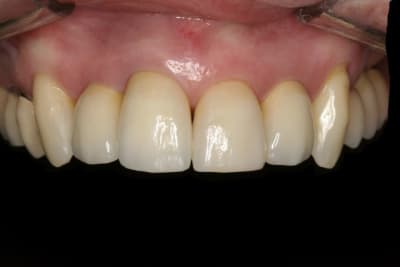

La suite avec les deuxièmes provisoires en places, le projet esthétique étant validé, les emp. ont été réalisées, ceramo-metal sur moignon composite a venir..

En ce qui concerne le choix entre ccc et ccm, il faut savoir que 90 % de mes couronnes sont en emax, mais dans le cas de racines extrêmement colorées ( ce qui est le cas ici)mon choix se porte sur des ccm classiques pour masquer ces colorations radiculaires que même une chape opaque sur emax ne peux dissimuler aussi bien qu'une ccm.